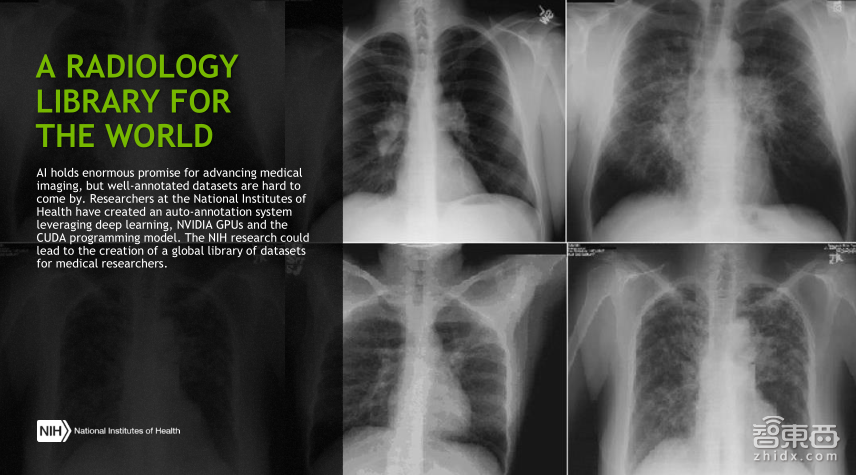

这张图展示的是一个library,即医学图像数据库,医学图像由于其敏感性和工作量,正规的注册数据集很难得到,但在诊断和治疗中非常关键, 是美国的国立研究院提出的一个注册系统,其实这就是一个获得数据集的方法。